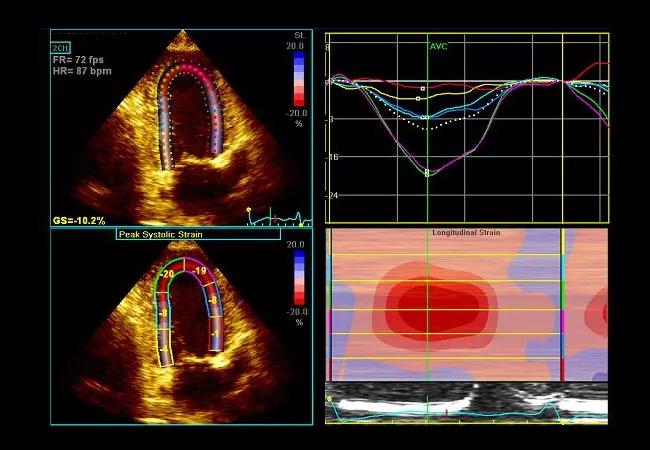

As shown in the image below, longitudinal strain demonstrated a distinctive apical sparing pattern.

The sum of apical segmental strain values was greater than the sum of mid and basal segmental strain values in the “bull’s eye” strain plot (image below), a finding that has been shown to be sensitive and specific for cardiac amyloidosis.